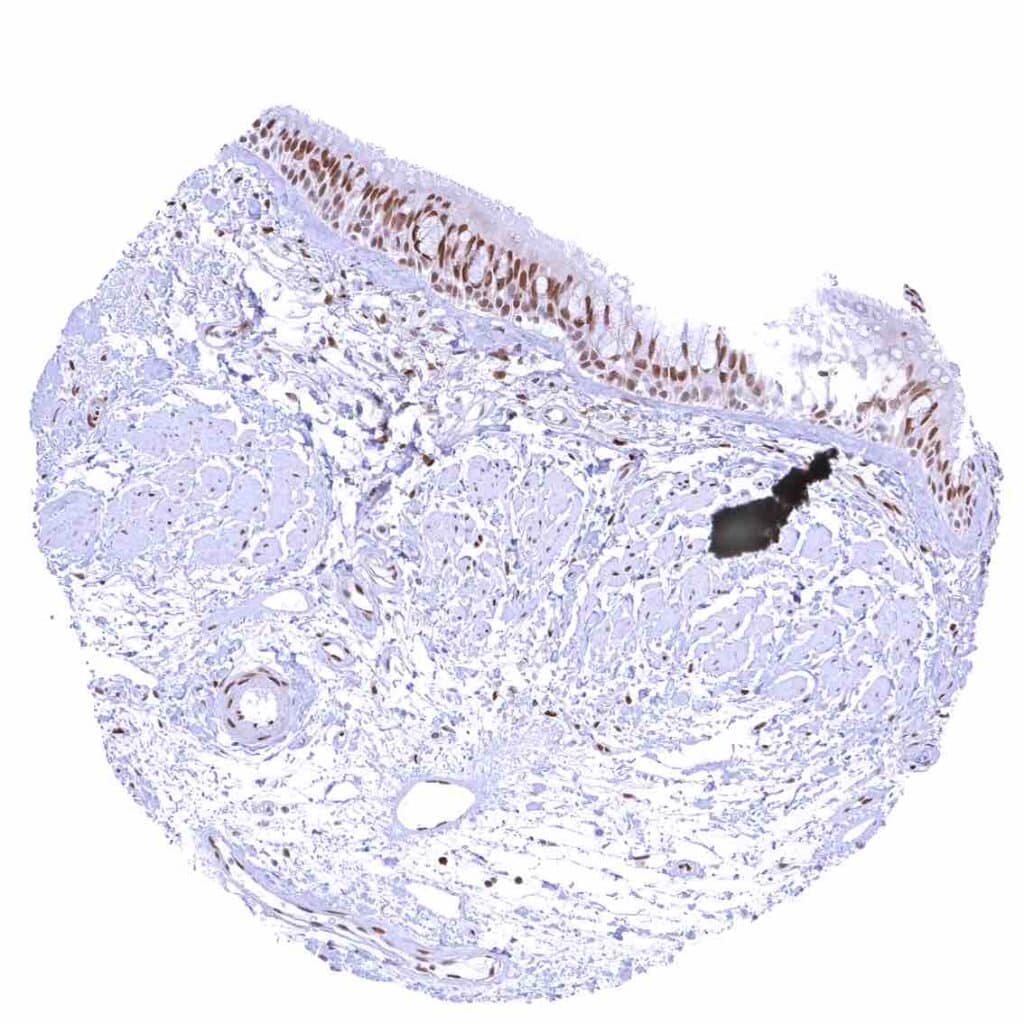

Appendix, mucosa – Among epithelial cells, nuclear p27 staining predominates in superficial epithelial cells. Most p27 staining occurs in lymphatic cells, however.